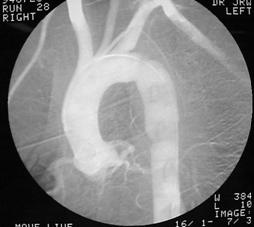

Lipsa vascularizatiei rinichiului stang Angiograma

Lipsa vascularizatiei rinichiului stang

Leziune renala prin impuscar Explozie de rinichi Angiograma